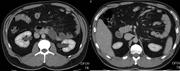

Pseudoaneurysm of the internal iliac artery resulting in massive per-rectal bleeding

T.I. Arthur and others

Journal of Surgical Case Reports, Volume 2013, Issue 10, October 2013, rjt069, https://doi.org/10.1093/jscr/rjt069